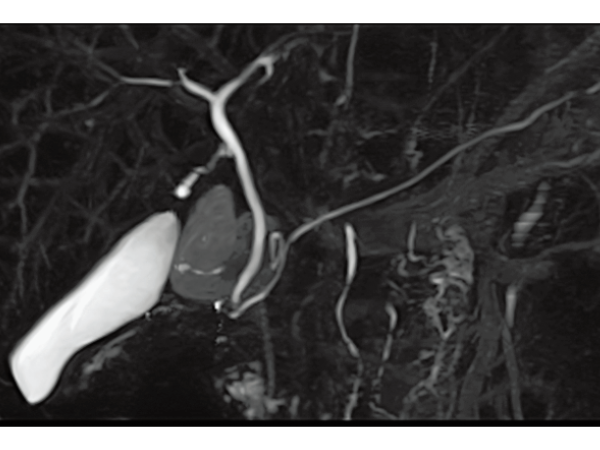

3DisoFSE MRCP (MIP) 呼吸同期, 2:50